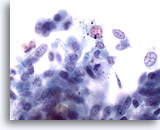

Figure 2

Bronchoalveolar lavage

Both macrophages and bronchial epithelial cells may be multinucleated. 40x

Bronchoalveolar lavage

Both macrophages and bronchial epithelial cells may be multinucleated. 40x

Figure 2

Bronchoalveolar lavage

Both macrophages and bronchial epithelial cells may be multinucleated.

40x

Bronchoalveolar lavage

Both macrophages and bronchial epithelial cells may be multinucleated.

40x